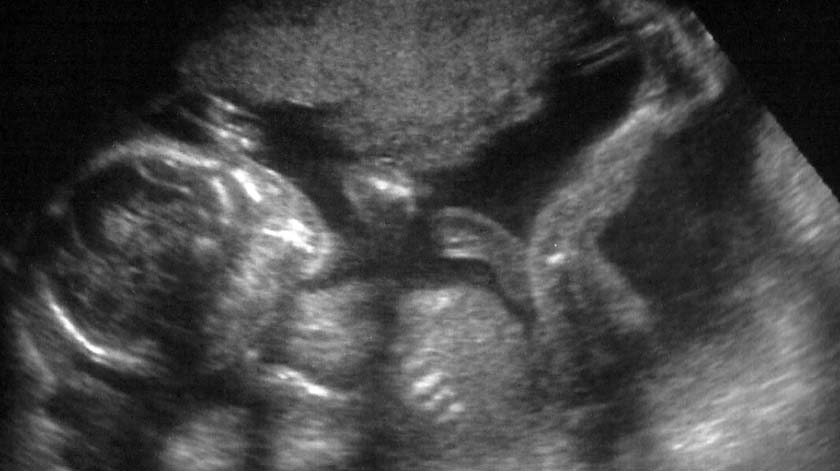

Via het UMC Amsterdam hebben we 10 setjes modelletjes aangeschaft en er zitten nog een aantal in de pijplijn. Dank aan de donateurs die dit mogelijk maakten. Deze handgemaakte modellen laten de ware grootte zien van ongeboren kinderen van zes, tot en met tien weken zwangerschap (gerekend vanaf de eerste dag van de laatste menstruatie). Zo kunnen wakers tijdens een gesprek laten zien hoe groot het kindje van de vrouw is en hoe het er uitziet. Het Fiom toont daarentegen op de website alleen een pluizig vruchtzakje als beeld van wat er zichtbaar is na de curettage als al het bloed, vocht en zacht weefsel is weggespoeld. Het UMC, laat de inhoud van het vruchtzakje zien. Het is maar welke boodschap je liever overbrengt.